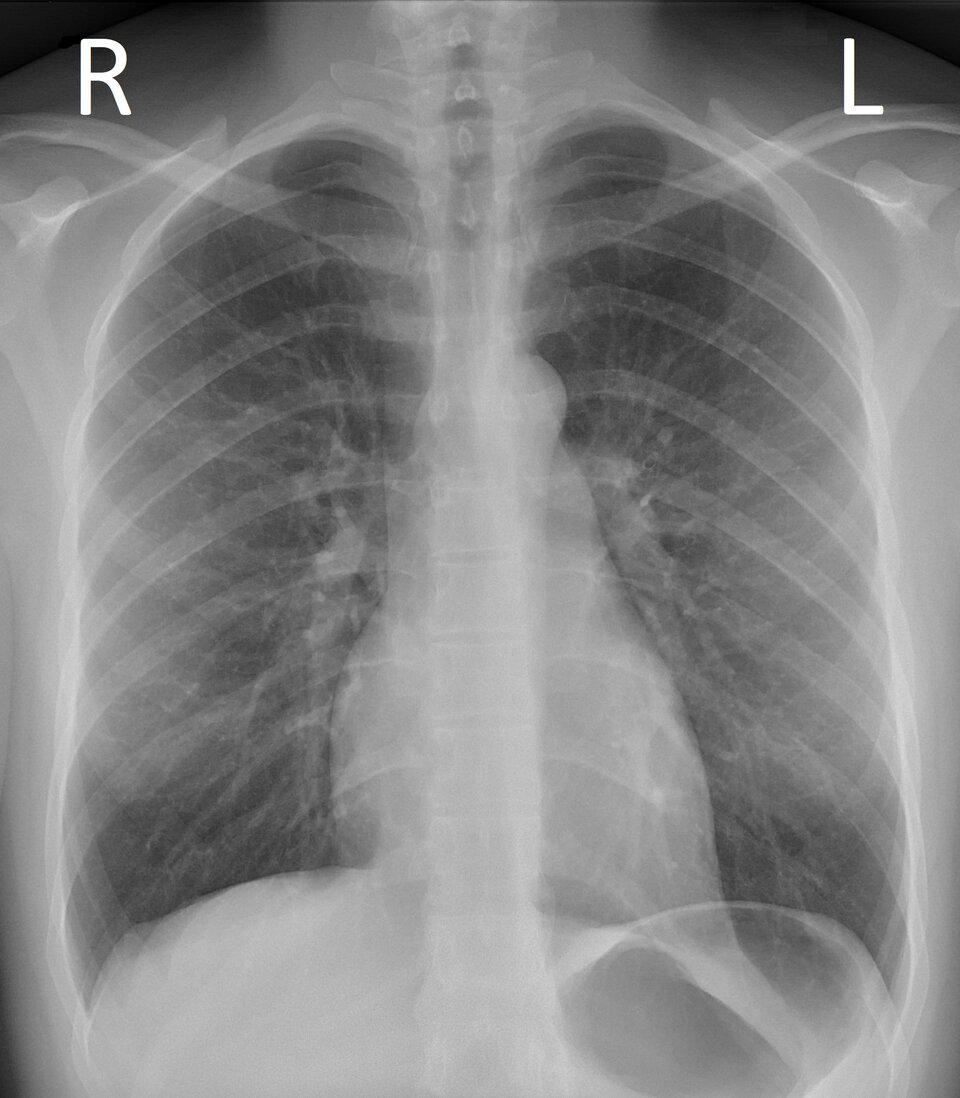

RTG płuc

RTG (rentgenografia) o badanie obrazowe wykorzystujące promieniowanie rentgenowskie do uzyskania obrazu narządów znajdujących się w klatce piersiowej. Jest badaniem szybkim, nieinwazyjnym i często wykonywanym jako podstawowa metoda diagnostyczna przy podejrzeniu chorób płuc (np. zapalenia płuc, gruźlicy, nowotworów),

Na zdjęciu radiologicznym (rentgenogramie, radiogramie, zdjęciu RTG) zaznaczone są strony pacjenta z perspektywy osoby stojącej z przodu. Prawa strona oznaczona jest literą R, a lewa literą L.

W opisie zdjęcia RTG lekarz posługuje się pojęciami przejaśnienie i zacienienie, jednak w przeciwnym znaczeniu tych słów. Przejaśnieniem nazywa miejsce, które widzi na zdjęciu jako zaczernienie, ponieważ promieniowanie zostało tam pochłonięte w nieznacznym stopniu. Natomiast w miejscu, które lekarz opisuje jako zacienienie, promieniowanie zostało pochłonięte w większej ilości i widoczne jest ono jako biały/jasnoszary fragment.